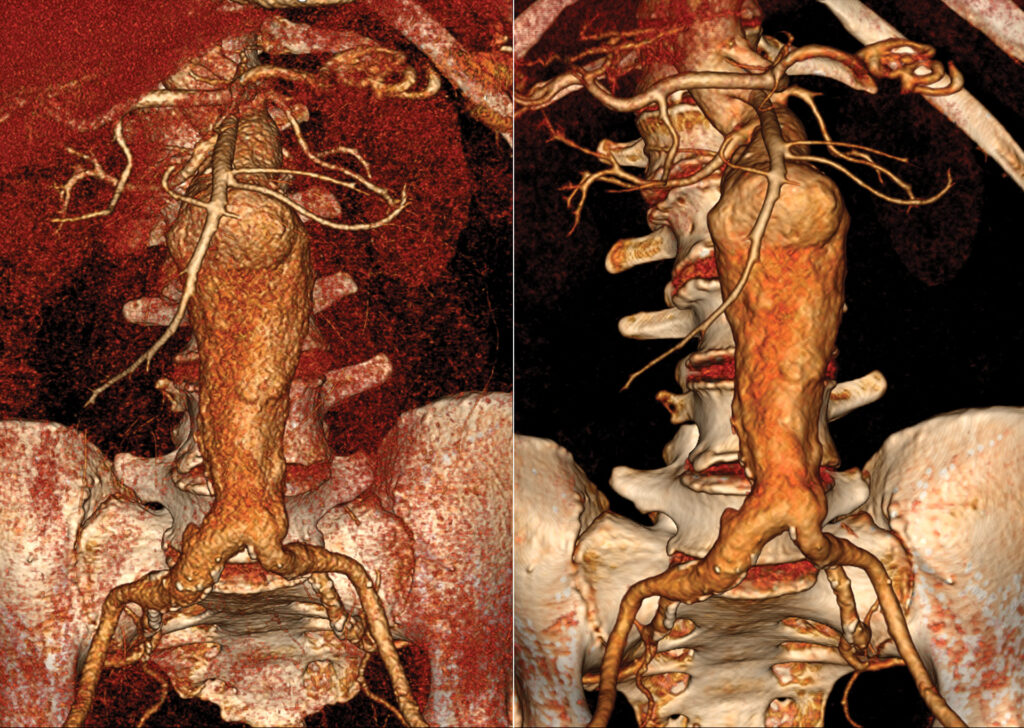

CT Aorta Analysis

CT Aorta Analysis enables users to visualize and evaluate the aorta vasculature.